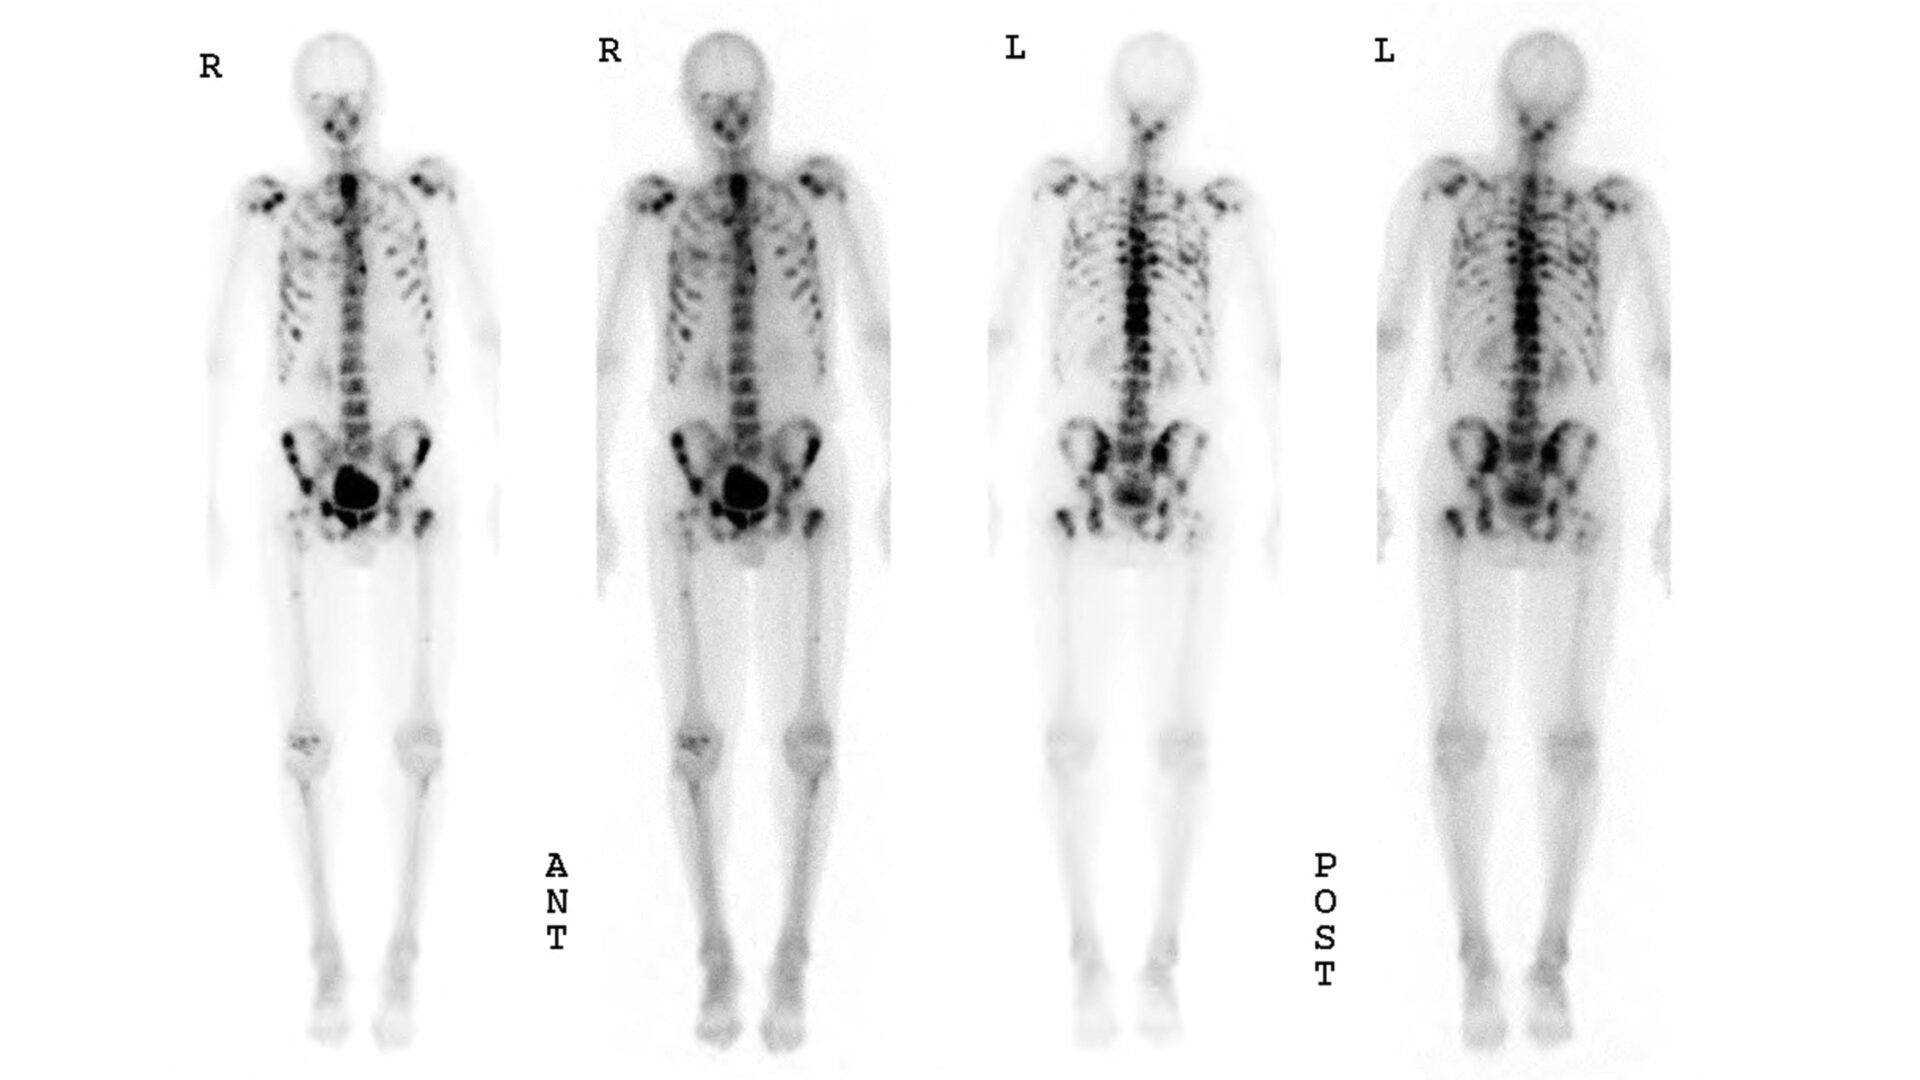

Before routine prostate-specific antigen (PSA) screening, prostate cancer was often diagnosed at an advanced stage, warranting radiographic staging prior to the initiation of treatment. However, since most new diagnoses today are clinically localized, the practice has become obsolete.

In their push for medical resource stewardship, the American Society of Clinical Oncology and the American Urological Association place significant emphasis on reducing the utilization of nuclear medicine bone scanning for early-stage prostate cancer.

• Among patients who underwent a bone scan in a guideline-discordant manner, 20.4 percent received this imaging during the control period compared with 14.9 percent during intervention (odds ratio=0.54; P=.04).

• Among patients for whom a bone scan was recommended by guidelines but was not performed, 6.8 percent received this guideline-discordant imaging during the control period compared with 5.5 percent during intervention (odds ratio=1.36; P=.36).